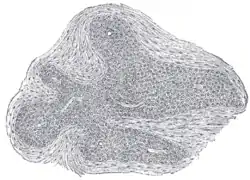

![]() Section of an irregular nodule of the glomus coccygeum. X 85. The section shows the fibrous covering of the nodule, the bloodvessels within it, and the epithelial cells of which it is constituted. | |

It is about 2.5 mm. in diameter and is irregularly oval in shape; several smaller nodules are found around or near the main mass.

It consists of irregular masses of round or polyhedral cells epitheloid cells, which are grouped around a dilated sinusoidal capillary vessel.